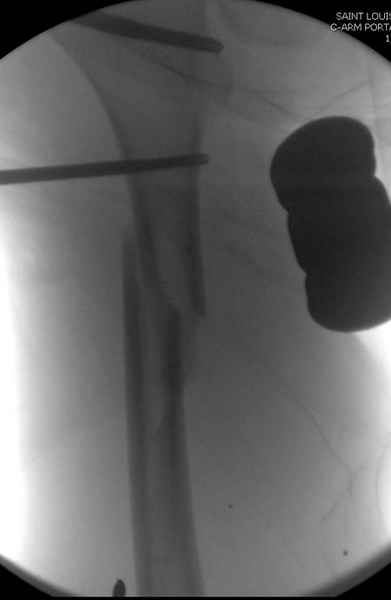

Второй случай тоже репозиция из малого доступа, больному 19 лет, множественные огнестрельные повреждениия конечностей, живота и черепа, правая конечность холодная, без пульсации. Ортопедический диагноз: огнестрельный перелом правого бедра. При срочной ангиографии повреждения сосудов не подтвердилось, конечность из-за ургентности состояния больного зафиксирована временным наружным фиксатором и больной оставлен на операционном столе для срочной лапаротомии хирургической службой.

Больной долго оставался нестабильным, только на 14 день удалось заменить на антеградный интромедуллярный штифт TFN (trochanteric femoral nail) SmithNephew. После неудачной попытки закрытой репозиции, несмотря на использование "joystick", проксимальный стержень от

наружного фиксатора, (перелом начал срастаться) репозицию провели из малого доступа, затем остальные этапы операции.